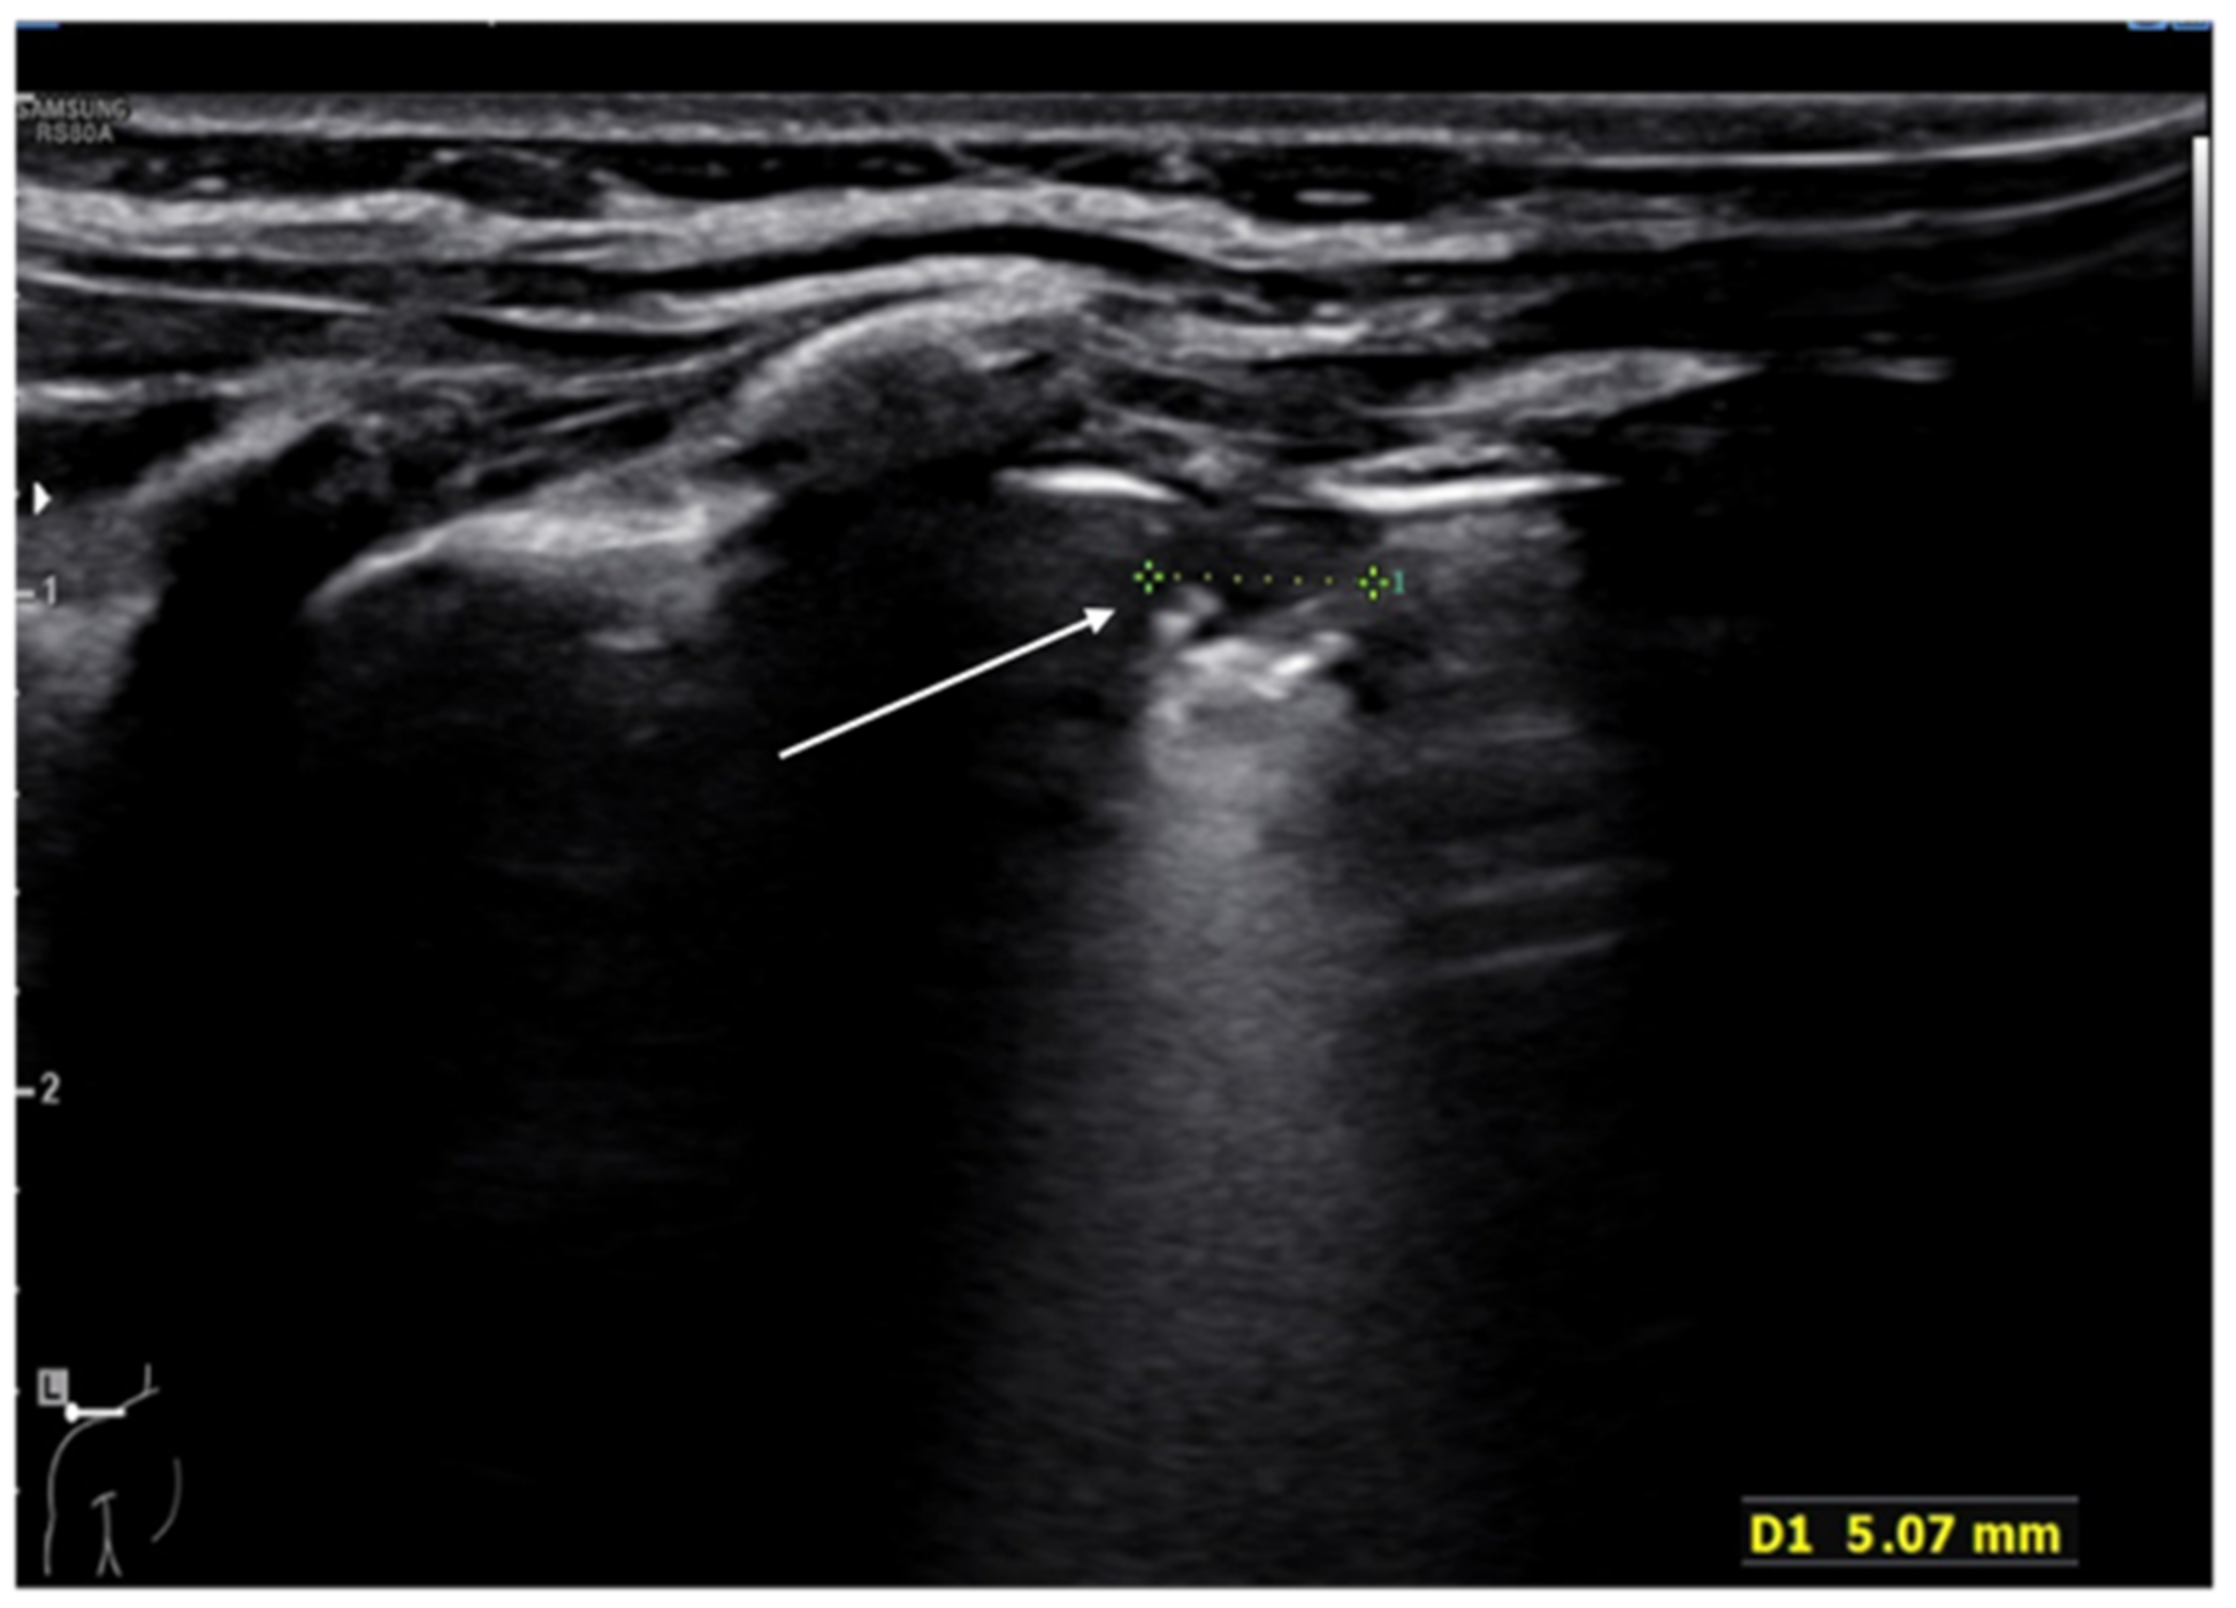

In addition, recent evidence has shown that ultrasounds may be a useful tool for the detection of bone fractures, in particular rib fractures [80]. A rib fracture is diagnosed when a discontinuity of the cortical alignment is observed as a clear disruption of the anterior echogenic margin of the rib (Figure 13). Furthermore, in the case of previous fractures, it is possible to observe at the ultrasound the bone callus that determines an irregular cortical profile different from that of the adjacent ribs. Rib fractures are suspected in pediatric age; in fact, they represent indicators of child abuse. Therefore, thoracic ultrasound could be helpful in identifying, promptly, children at risk of abuse, reducing the exposure to ionizing radiation [81,82].

Figure 13.

Rib fracture in transverse scan along the major axis of the rib (white arrow).